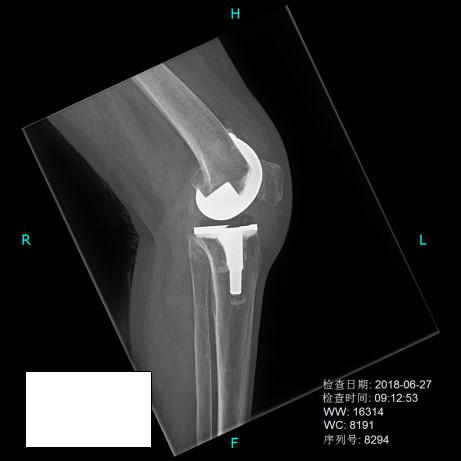

人工膝关节表面置换术